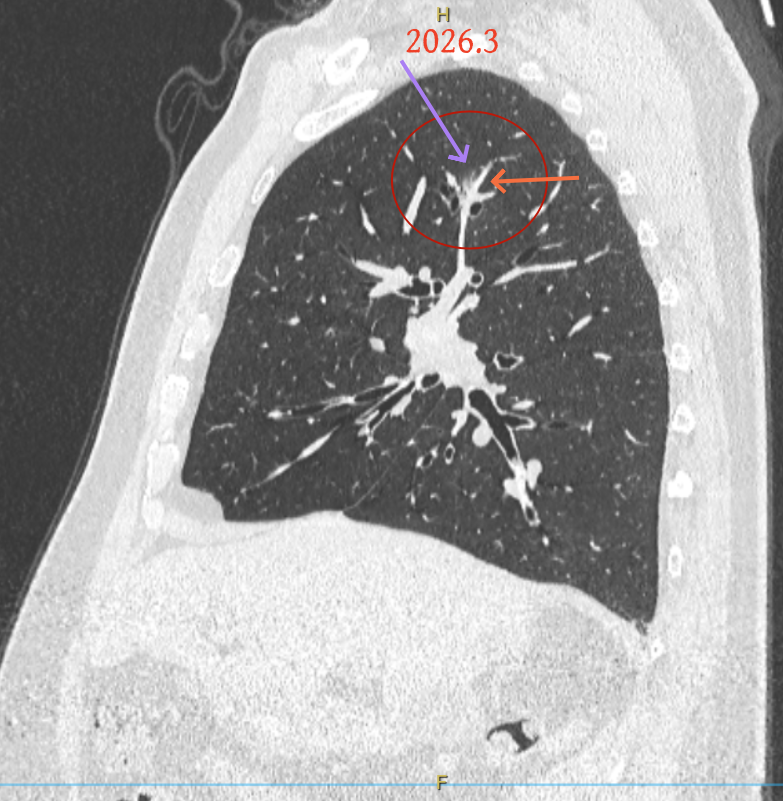

第三次问诊:2026.3

影像展示与分析:

再看2026年3月最近复查时不同层面病灶A的细节影像特征:

微小血管走向病灶,磨玻璃的密度淡而较纯。

再看病灶B的2026年3月细节影像特征:

边缘位置也是较淡的磨玻璃成分。

上图是混合密度,轮廓较清,瘤肺边界欠清晰。

病灶A以及他处磨玻璃结节其实进展都是不明显的,略与2022年比,病灶A稍显明显点。病灶B开始时极淡,之前进展虽有但也甚微,直到2025年9月仍是磨玻璃成分为主,只是点状少许密度稍高成分。但在最近半年内却显然进展!若从影像上判断,基本上就得是浸润性腺癌了。那有几点:一是必不能再随访;二是大小来看仍是1A期;三是从快速进展来说,可能含有部分高危亚型,比如微乳头或实体型等;四是他处的磨玻璃结节以及病灶A显然不能用病灶B的转移来解释,仍考虑是多原发早期肺癌。

这是较为少见的一个病例,磨玻璃为主,而且一直瘤肺边界欠清晰的病灶何以会在之前三年均极缓慢微小变化的情况下,近半年却快速进展呢?从影像细节上看,我们能否进一步分析哪种纯磨玻璃结节可能会较快进展?结合本例,我个人的考虑是:1、病灶整体显得是磨玻璃密度,但灶内并不均匀,就如磨玻璃密度中混入细沙状;2、整体轮廓虽然较清但瘤肺边界相对来说却并不太清晰;3、邻近有血管紧挨,而且与病灶这间缺乏间隙;4、病灶密度不高,没有明显实性成分,却有灶内有细支气管通气征,说明肿瘤成分具有收缩力,却与纯磨的收缩不匹配(纯磨一般不太会有明显收缩力)。如果有上面这些特征可能要提高警惕,一是适当较短的随访间隔,二是影像细节变化要更加注意,开始变化意味着已经进入发展期,而非蛰伏期。当然是否在2025年9月时定得手术了?如果是孤立性的病灶B,且位置位于能简单楔形切除的位置,那是可以考虑的。但位置深、两肺多发,切除范围不小,再今年据肺癌诊疗指南中说的混合磨玻璃结节实性成分不足25%是非侵袭性病变,且几乎不会转移,那么按原则仍再随访显然是可以的。本例的随访变化再次表明磨玻璃密度肺癌的诊疗个体化之路仍是很漫长的,按指南原则的随访或诊疗显然不足以覆盖所有病例,总结与经验积累永远在路上。